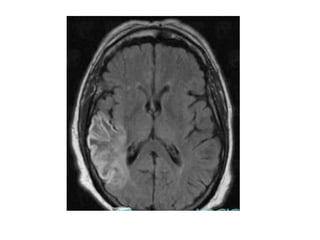

FLAIR image demonstrating high signal in the left thalamus , there is also high

signal in the basal ganglia on the right, these bilateral findings should raise

the suspicion of deep cerebral venous thrombosis, a sagittal CT

reconstruction demonstrates a filling defect in the straight sinus and the

vein of Galen (arrows)